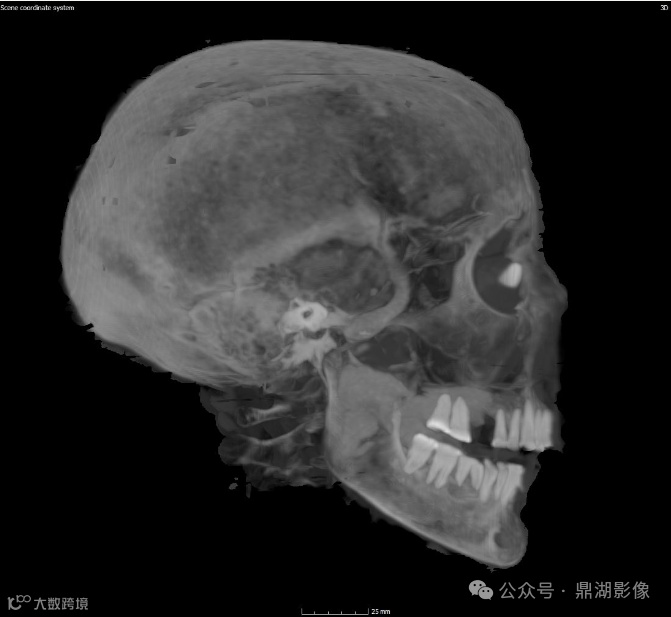

颅脑图像

现在可以断定她去世时的年龄为30多岁或40岁出头;

她失去了几颗牙齿,剩余牙齿严重磨损,这表明她吃的食物中含有对牙釉质有损害的散沙颗粒;

扫描结果还显示,Chenet-aa夫人的眼窝中还植入了辅助眼球。